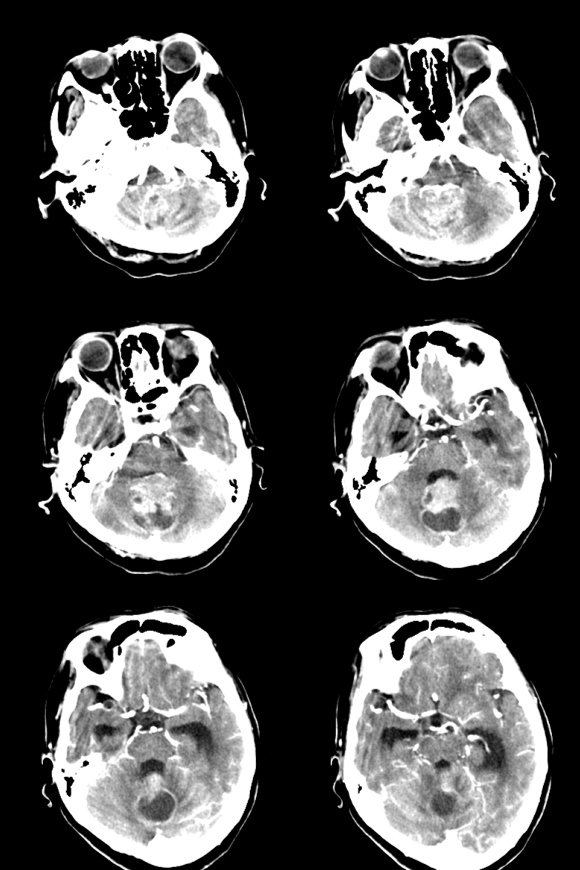

标题: CT18179:F67y,反复头昏、头痛。 [打印本页]

标题: CT18179:F67y,反复头昏、头痛。

67岁女性,头昏、头痛1年+。

小脑蚓部血管母细胞瘤伴脑室扩张积水。

考虑:小脑蚓部血管母细胞瘤伴脑室扩张积水。

支持考虑:小脑蚓部血管母细胞瘤伴梗阻性脑积水。

1、小脑薄壁环状强化囊状影。

2、脑膜明显强化。

3、病史一年多。

这个病人如有个磁共振就好了,在t2信号上血管母细胞瘤为长t2信号,而结核为等t2或稍短t2,因为其内为干酪样坏死。(干酪样坏死:其内容物类似脂质,质地较实,均匀细腻)

血管母细胞瘤一般呈囊性,周围无水肿,增强可见壁结节!此瘤这几种征象没有!

考虑星形细胞瘤或室管膜瘤!!

首先考虑小脑蚓部血管母细胞瘤伴梗阻性脑积水。鉴别诊断转移瘤。

该年龄段本部位好发肿瘤有:星形细胞瘤;室管膜瘤;脉络膜肿瘤;血管母细胞瘤;转移瘤;

征象:肿块形态欠规整,境界欠清,可见实性和囊性两部分,囊性部分增强可见壁有强化;实性部分有囊变坏死,增强强化明显;

拟诊:室管膜瘤;

讨论:星形细胞瘤:增强强化程度不应有如此明显/均匀;

脉络膜肿瘤:囊变 坏死少见;

血管母细胞瘤:好发于小脑半球,多为大囊小结节型,增强特有的亮灯征不明显,且其壁应该无强化;

转移瘤:无明确原发灶,且其好发于皮髓质交界处;